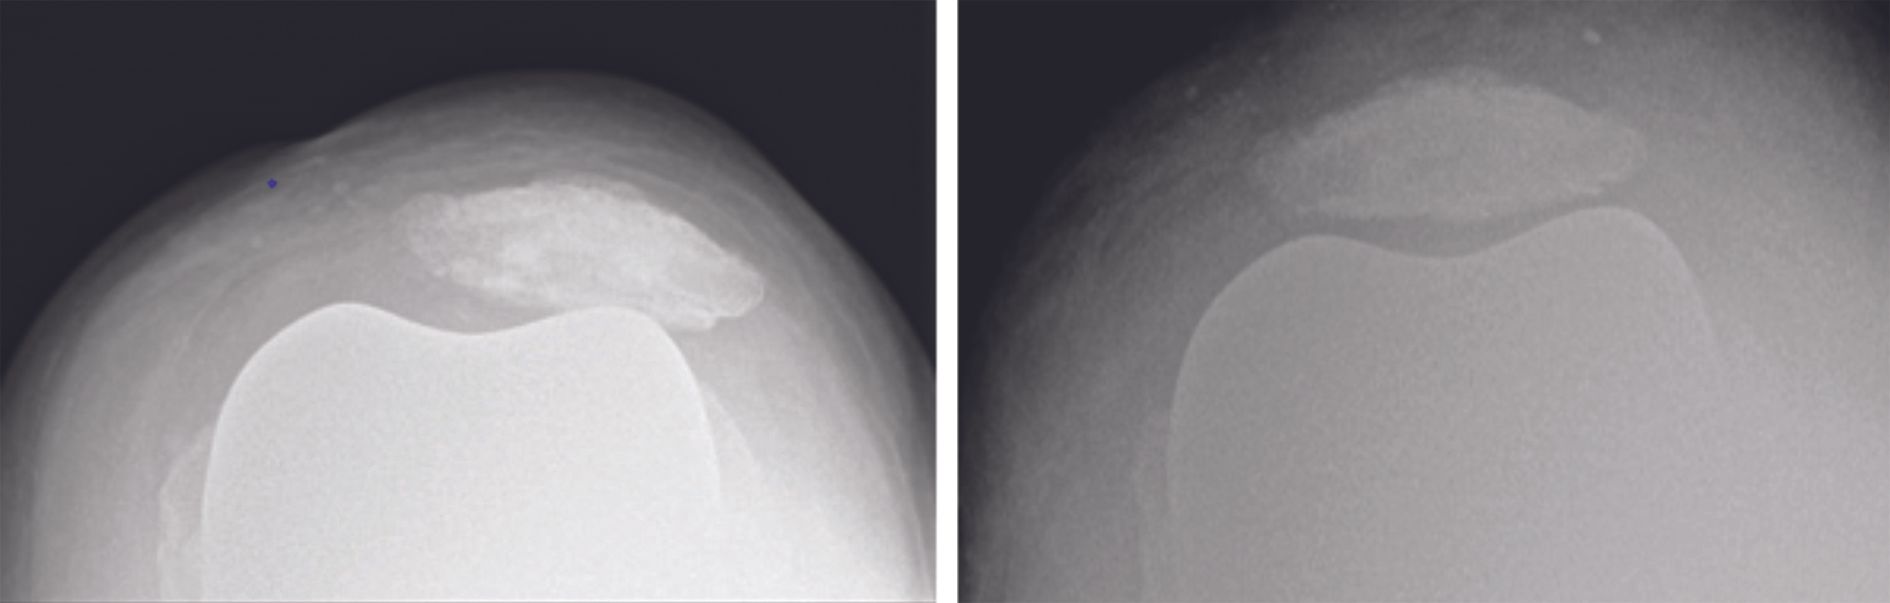

Our indications for MPFL reconstruction in TKA are selective and restricted to patellar instability, eccentricity or tilt, where the implant was initially correctly positioned (Fig. 11). It is important to understand that any soft tissue procedure will fail over time without correcting the malpositioned components. During revision surgery for malposition of the components additional MPFL might be helpful.

There is not much literature on this subject, but the results are relatively good. As well as the first case described by Asada,[13] who recorded no dislocation recurrence at two years, Gotto et al.[21] also describe a case involving a 78-year-old lady who had ruptured the medial arthrotomy sutures and presented with permanent patellar dislocation. There was no evidence of patellofemoral instability at the one-year follow-up. Gennip et al.[22] report on a series of nine MPFL reconstructions with systematic lateral release and two ATT transfers. They used the quadriceps tendon if viable, otherwise they opted for a tendon allograft fixed using two anchors. A median follow-up of 33 months they found no new dislocations. Lamotte et al [23] review six cases of MPFL reconstruction using a gracilis autograft and two anchors for fixation. One reconstruction was combined with a change of implant (combined internal rotation 8°). No patient suffered any dislocation recurrence and clinical scores improved across the board. This same series also includes the particular case of an 81-year old man with a long medical history who presented with permanent patellar dislocation due to internal femoral rotation of 7°. Revision was deemed too risky so only MPFL reconstruction was performed. He still experienced subjective instability, but there was no dislocation recurrence. There is little consensus for which TKA knees with PFI such ‘palliative’ procedures of MPFL reconstruction or TTO with medialization of the tibia tubercle are indicated to compensate for components malrotation without revision surgery. In selected patients it represents an interesting option because it has low morbidity and can offer a simple solution for patients where revision is tricky and there is a reliable expected functional benefit.